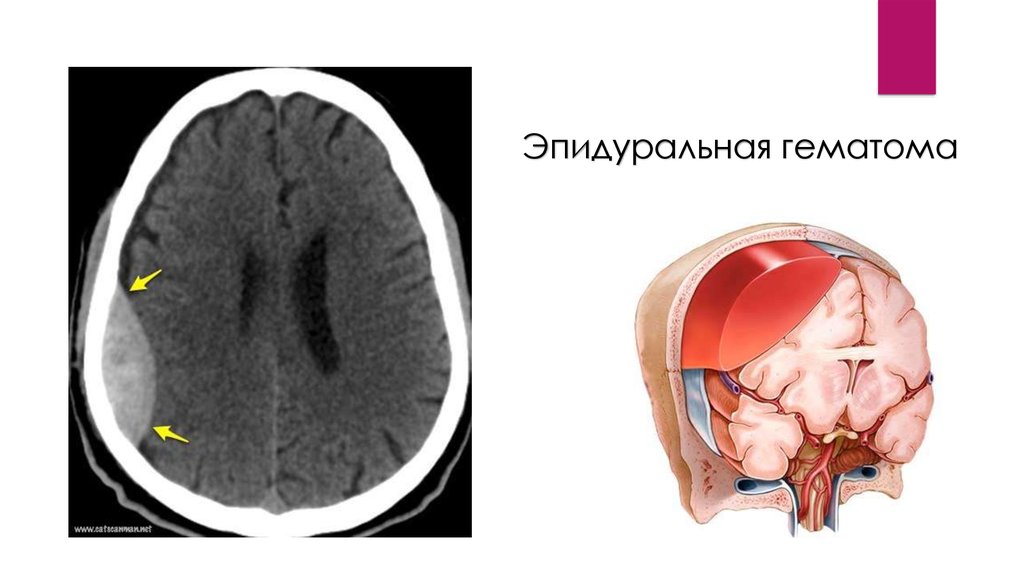

Эпидуральная гематома

эпидуральные